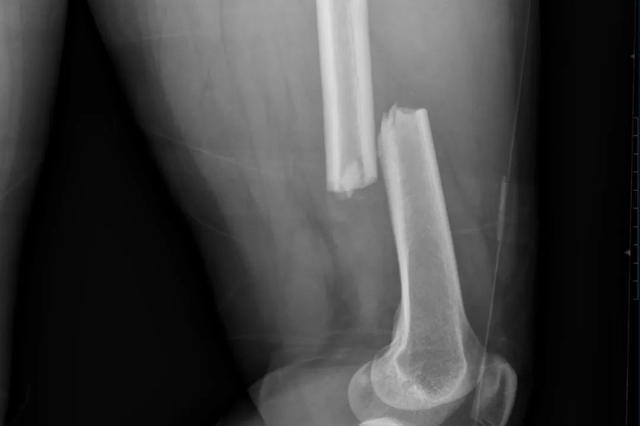

这场意外不仅让她的股骨遭遇罕见的“双段骨折”——左股骨干与转子间两处严重移位,更将骨二科团队推向了技术与勇气的双重考验。

接诊医生张程触诊时感受到明显的骨块错动,影像检查印证了最棘手的判断:患者左股骨如同被暴力折断的树枝,近端转子间与中段骨干同时出现不稳定性骨折。

这种“一骨双折”的罕见病例,具备明确手术指征。传统手术方案需在患者左大腿上下段都开刀,植入两块钢板进行固定,切口长度几乎贯穿大腿,手术风险、医疗费用与漫长康复期均令王女士望而却步。

(术前)